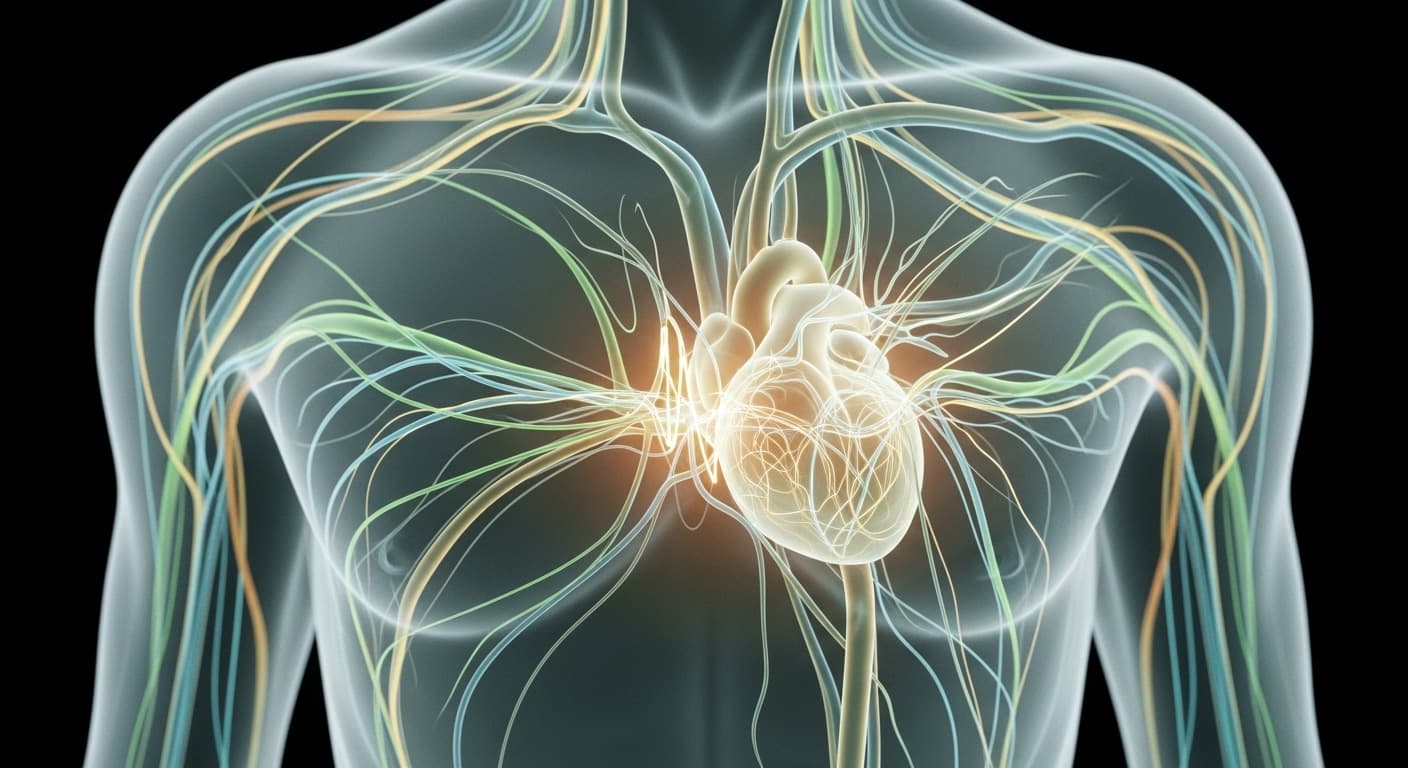

가끔 느껴지는 심장의 엇박자, '가슴이 쿵 내려앉는 느낌'은 현대 의학에서는 주로 '심계항진'이나 '부정맥'의 한 형태로 설명됩니다. 특히 가장 흔한 것이 바로 '조기 박동(Premature Beats)'인데요, 심실 조기 수축(PVC, Premature Ventricular Contraction)이나 심방 조기 수축(PAC, Premature Atrial Contraction)이 여기에 해당해요. 심장이 한 박자 빨리 뛰고 나면 다음 박자는 보상적으로 잠깐 쉬었다 뛰기 때문에, 마치 심장이 쿵 하고 내려앉는 듯한 느낌이나 건너뛰는 듯한 느낌을 받게 되는 거죠. 이러한 조기 박동은 사실 건강한 사람에게도 흔히 나타날 수 있어요. 스트레스, 불안, 과도한 카페인 섭취, 흡연, 음주, 수면 부족, 심한 피로 등이 주요 원인으로 꼽히죠. 우리 몸의 자율신경계, 즉 교감신경과 부교감신경의 균형이 깨지면 심장 박동에 영향을 미치게 되는데, 스트레스는 교감신경을 과도하게 활성화시켜 심장을 더 흥분하게 만들어요. 또한, 전해질 불균형(특히 칼륨, 마그네슘 수치), 갑상선 기능 항진증, 특정 약물 복용 등도 조기 박동을 유발할 수 있습니다. 대부분은 특별한 치료 없이도 괜찮지만, 잦거나 심한 경우, 혹은 어지럼증, 실신, 흉통 등의 다른 증상을 동반한다면 심장 질환의 신호일 수도 있으니 반드시 전문의의 진료를 받아보는 것이 중요해요. 동의보감에서 말하는 '기혈 응체'는 현대 의학의 관점에서 보면 스트레스로 인한 자율신경계 불균형, 혈액순환 저하, 만성 염증 반응 등 복합적인 요인들이 심장 건강에 영향을 미치는 것과 맞닿아 있습니다. 단순히 심장의 문제가 아니라, 몸과 마음의 유기적인 연결 속에서 발생하는 현상이라는 점을 현대 의학도 인정하고 있어요. 그래서 이러한 증상이 있을 때는 단순히 증상만 억제하는 것보다, 내 몸과 마음의 균형을 되찾기 위한 전반적인 노력이 필요하다고 조언하는 거죠. 내 몸이 보내는 신호에 귀 기울이는 것이 가장 중요해요.